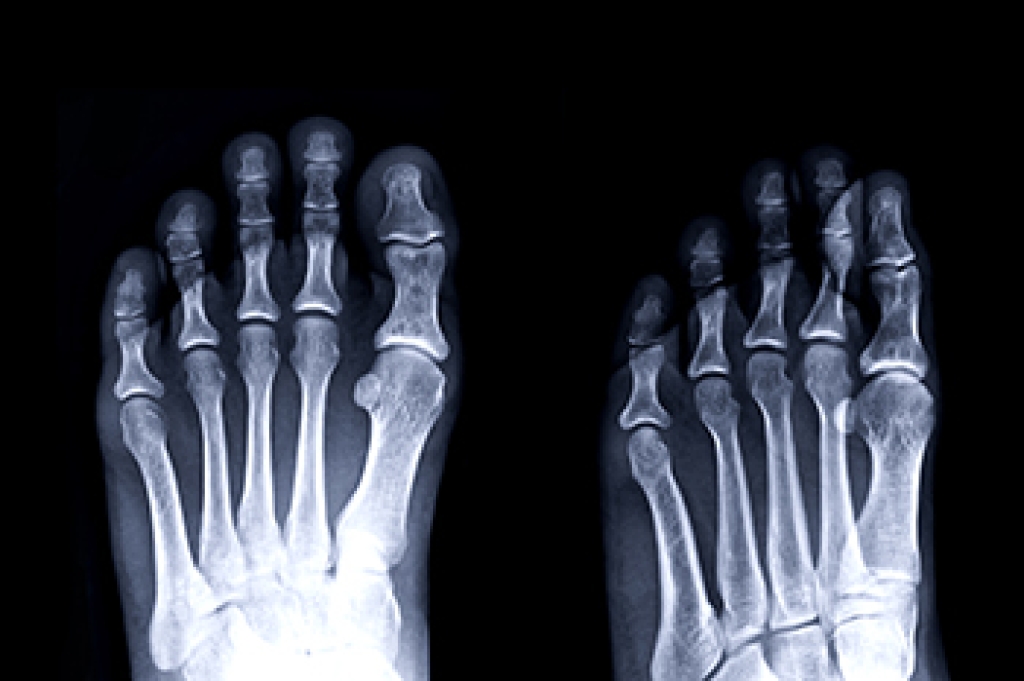

Plantar fasciitis is a common foot condition that gradually develops for various reasons. These can include wearing shoes that do not fit correctly or from gaining weight. Standing on hard or uneven surfaces for most of the day or from recently increasing speed while running can also increase your chance of getting plantar fasciitis. The plantar fascia is found on the bottom of the foot and is the band of tissue that connects the heel to the toes. Any one of the above reasons may cause the plantar fascia to become irritated or torn, and this can lead to plantar fasciitis. Mild relief may be found when specific heel stretches are performed, in addition to wearing shoes that have a cushioned heel. It may help to lose weight if applicable, and elevating the foot frequently may reduce the discomfort. Orthotics may be worn that can provide the necessary support as the foot heals. If you have heel pain, it is suggested that you visit a podiatrist who can treat plantar fasciitis.

Plantar fasciitis is the inflammation of the thick band of tissue that runs along the bottom of your foot, known as the plantar fascia, and causes mild to severe heel pain.